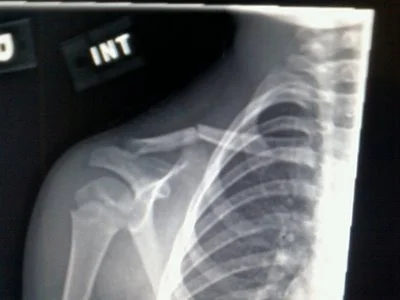

What do you bring someone who is in hospital for a long time, other than flowers? Food is not allowed. Novels can be challenging to read when you're pumped with drugs and navigating pain. In the works, is a "coffee table" type book, filled with stories and pictures of people who accomplished great things while ill or bed-ridden, beautiful renderings of the human body and its great capacity, as well as room to personally document the hospital experience. It's funny, beautiful and tender gift for people in hospital. Easy to flip through, easy on the eyes and filled with the quiet beauty and lonely ache that is lying in a hospital bed.

a hospital Chronology:

5 spinal surgeries

1 staff infection

1 allergic reacting to contrast fluid

Total number of week in bed: 16